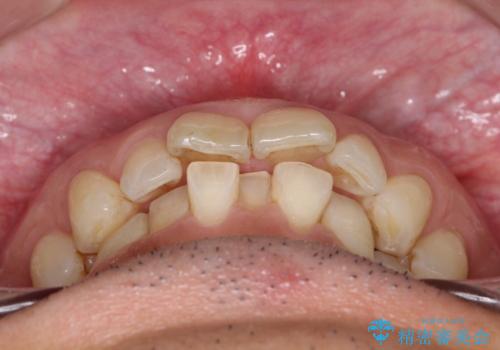

【インザライン】前歯の凸凹を治したい

- 前歯の凸凹を主訴に来院されました。

下顎位が右方に変異しており、外科矯正も提案しましたが患者様は希望されず、インビザラインにて治療を完了しております。

叢生のスペースを確保するために、臼歯部の遠心移動を行っています。

今回の治療計画は上顎の正中を顔と揃えることを優先しています。